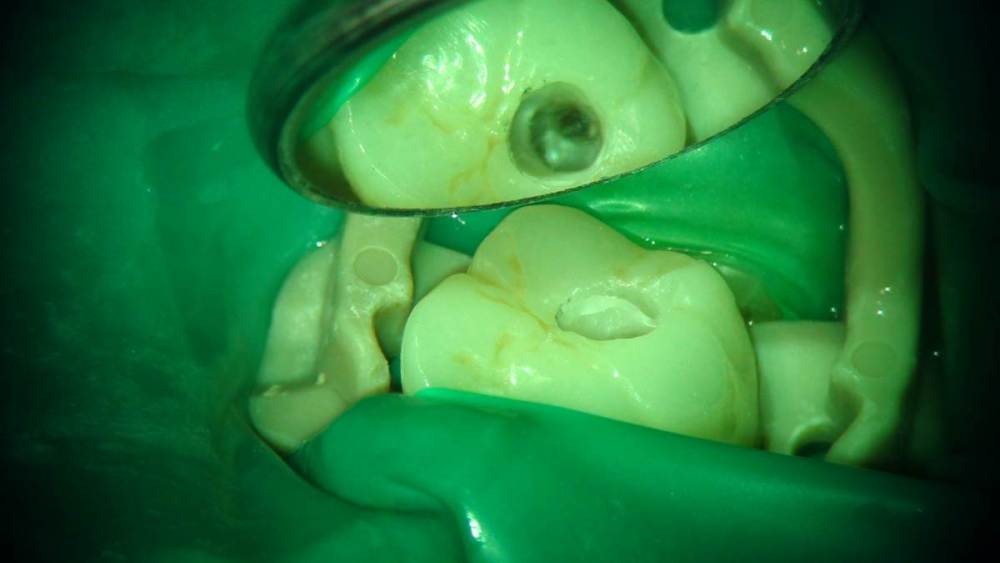

Ico Опубликовано 10 апреля, 2022 Автор Поделиться Опубликовано 10 апреля, 2022 (изменено) 3 отдельных канала в нижнем премоляре,паковка похожая как у Томаса Ланга.Каллибровка,паковка апексов была по S2 протейперу + 25 к. Изменено 10 апреля, 2022 пользователем Ico 1 1 2 Ссылка на комментарий